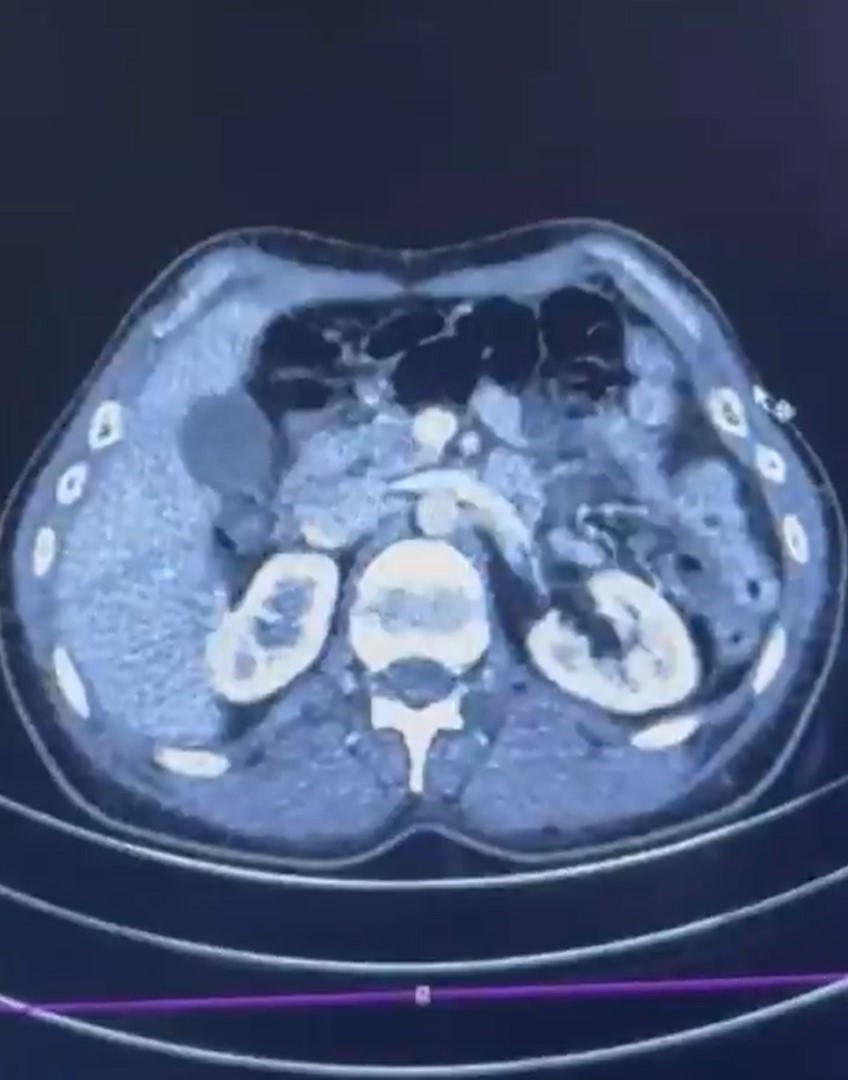

Şüphelilerden S.C. ve R.B.C.’nin Kayseri Şehir Hastanesi’nde yapılan iç beden muayenelerinde, mide bölgesinde yabancı madde tespit edildi. Hastanede gerçekleştirilen kontroller sonucunda, iki şahsın vücudundan kapsül şeklinde paketlenmiş toplam 50 adet uyuşturucu madde çıkarıldı. Ele geçirilen maddenin toplam ağırlığının 554 gram olduğu belirlendi. Maddelerin, ülkeye mide yoluyla sokulduğu değerlendiriliyor.